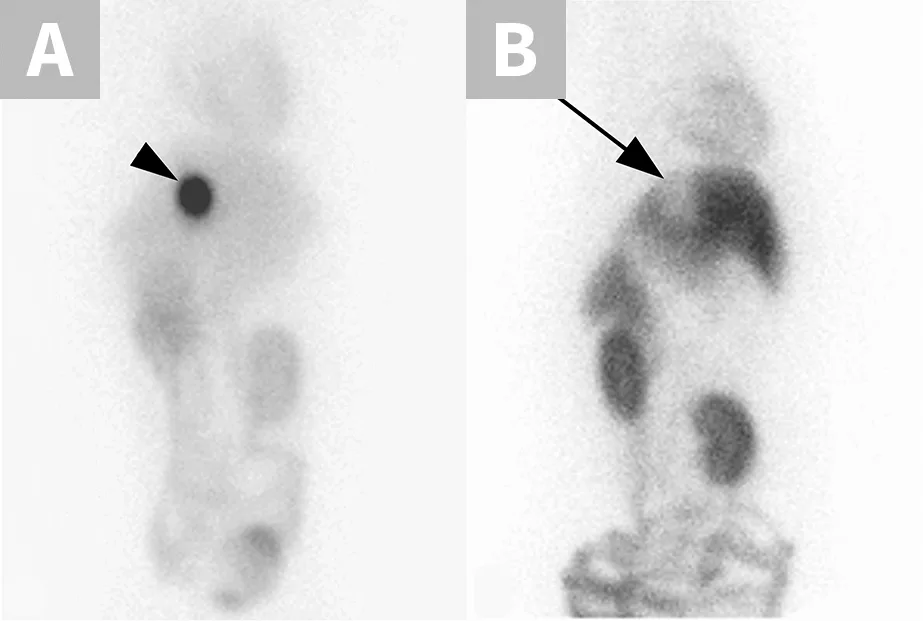

P-glycoprotein, encoded by the multidrug sensitivity gene (MDR1 gene, also known as ABCB1 gene), functions as a drug transport pump at the blood-brain barrier, preventing potentially toxic compounds from gaining access to the brain.1 The MDR1 gene mutation (ABCB1-∆) results in production of dysfunctional P-glycoprotein and affects many herding breed dogs (Table 1) and some nonherding breeds.2 Drugs that are P-glycoprotein substrates achieve higher brain concentrations in dogs with the MDR1 mutation (heterozygous or homozygous) than in dogs without the mutation.1 When P-glycoprotein substrate drugs exert CNS effects, those effects are more pronounced in dogs with the MDR1 mutation unless the dosage is decreased appropriately.1,3 Thus, dose reductions should be made when possible or an alternative drug should be selected. A nuclear scintigraphy study demonstrated that wild-type MDR1 homozygotes (MDR1 normal/normal) have a fully functional blood-brain barrier with essentially no radioactivity in the brain, whereas MDR1 mutant homozygotes (MDR1 mutant/mutant) have brain radioactivity levels comparable with surrounding tissue, demonstrating a dysfunctional blood-brain barrier with respect to P-glycoprotein substrates (Figure 1).1 Although many P-glycoprotein substrate drugs (Table 2) exert CNS effects and cause neurologic toxicity in dogs with the MDR1 mutation, some do not and can therefore be administered at usual dosages. MDR1 genotyping should be performed to identify at-risk dogs prior to treatment with P-glycoprotein substrate drugs.4

FIGURE 1

Nuclear scintigraphic images of the brain and surrounding tissue in collies after IV injection of the radiolabeled P-glycoprotein substrate sestamibi (99mTc-sestamibi). P-glycoprotein restricts 99mTc-sestamibi entry into brain tissue of the MDR1 wild-type dog (A), whereas lack of P-glycoprotein allows 99mTc-sestamibi to enter brain tissue of the MDR1 mutant/mutant dog (B).